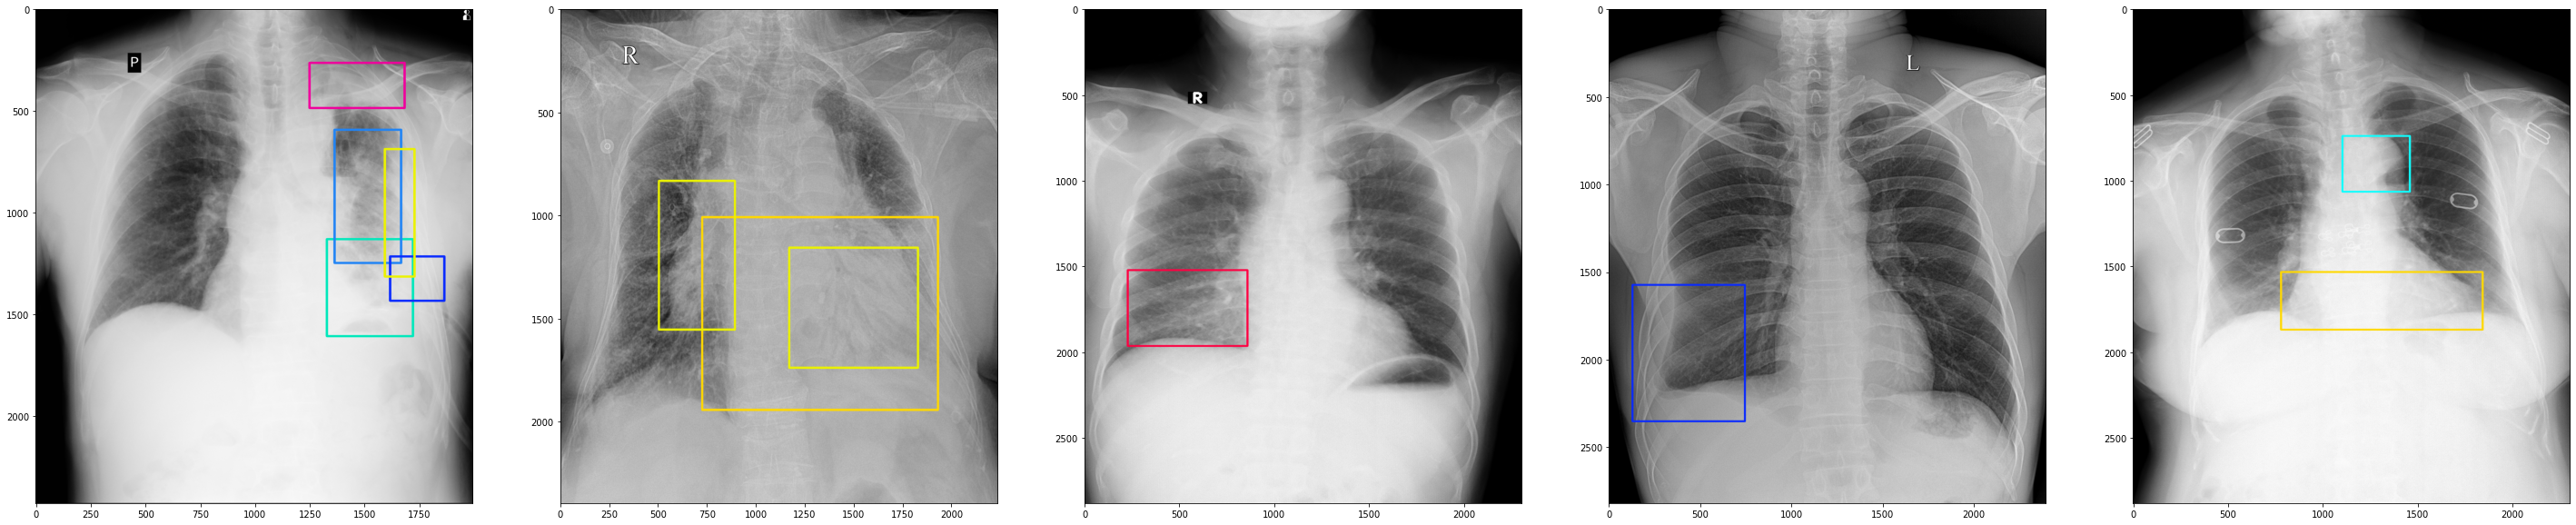

VinDr-CXR [5], by far the largest public chest X-ray database with radiologist-generated annotations. It consists of 18,000 chest X-ray scans that come with both the localization of critical findings and the classification of common thoracic diseases. The dataset includes 15,000 scans for training and 3,000 scans for testing. In particular, the annotations were obtained by a group of 17 radiologists with at least eight years of experience. Each image in the training set was independently labeled by three radiologists, while the annotations in the test set were carefully treated and obtained by the consensus of 5 radiologists. Several examples from the VinDr-CXR dataset are shown in Figure 5.

Refer to caption

(a)

(b)

Figure 5: Visualization of abnormal findings (different bounding box colors represent different findings) from the VinDr-CXR dataset: (top) Each scan in the training set was annotated by three different radiologists; (bottom) Test set annotations were obtained from the consensus of five radiologists.